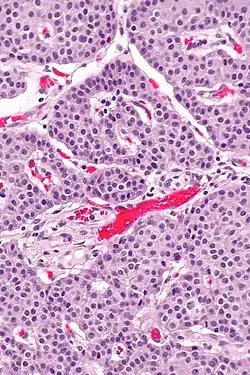

![]() Micrografía de células APUD en el intestino delgado conformando un tumor neuroendocrino. Arriba se ve el fondo de varias criptas, con forma de fondo de saco. Mediano aumento.. hematoxilna eosina | ||